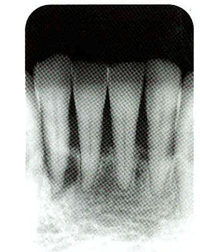

歯周病かどうかを調べるには、

歯周ポケットの測定が有効です。

プローブという器具を使って、

歯と歯ぐきの間の深さを測ります。

だいたい3mm以下が健康な人の深さです。

また、測る時に、出血があると、

歯周病にかかっている

可能性が高くなります。

歯周ポケットの測定

健康な歯と歯ぐきは、適度に密着し、すき間などはほとんどありません。

しかし、歯周病になると、歯ぐきが弱くなり、歯とのすき間が出来ます。

これを確かめるのが、歯周ポケットの測定です(3mm以下が正常)。